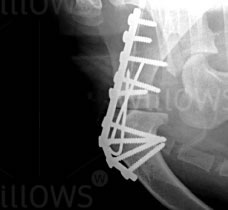

Pic 1: Arthrodesis of a shoulder joint in a terrier breed